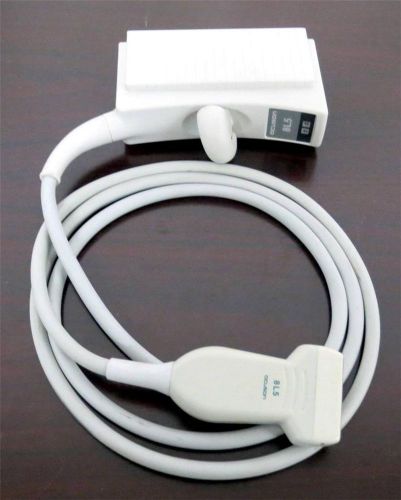

US $1300

| “30 Day Warranty! Works great!” |

| Brand | Aloka |

| Model | SSD-500 |

Acuson 8L5 Vascular Ultrasound Transducer Probe Sequoia Linear Array WARRANTY